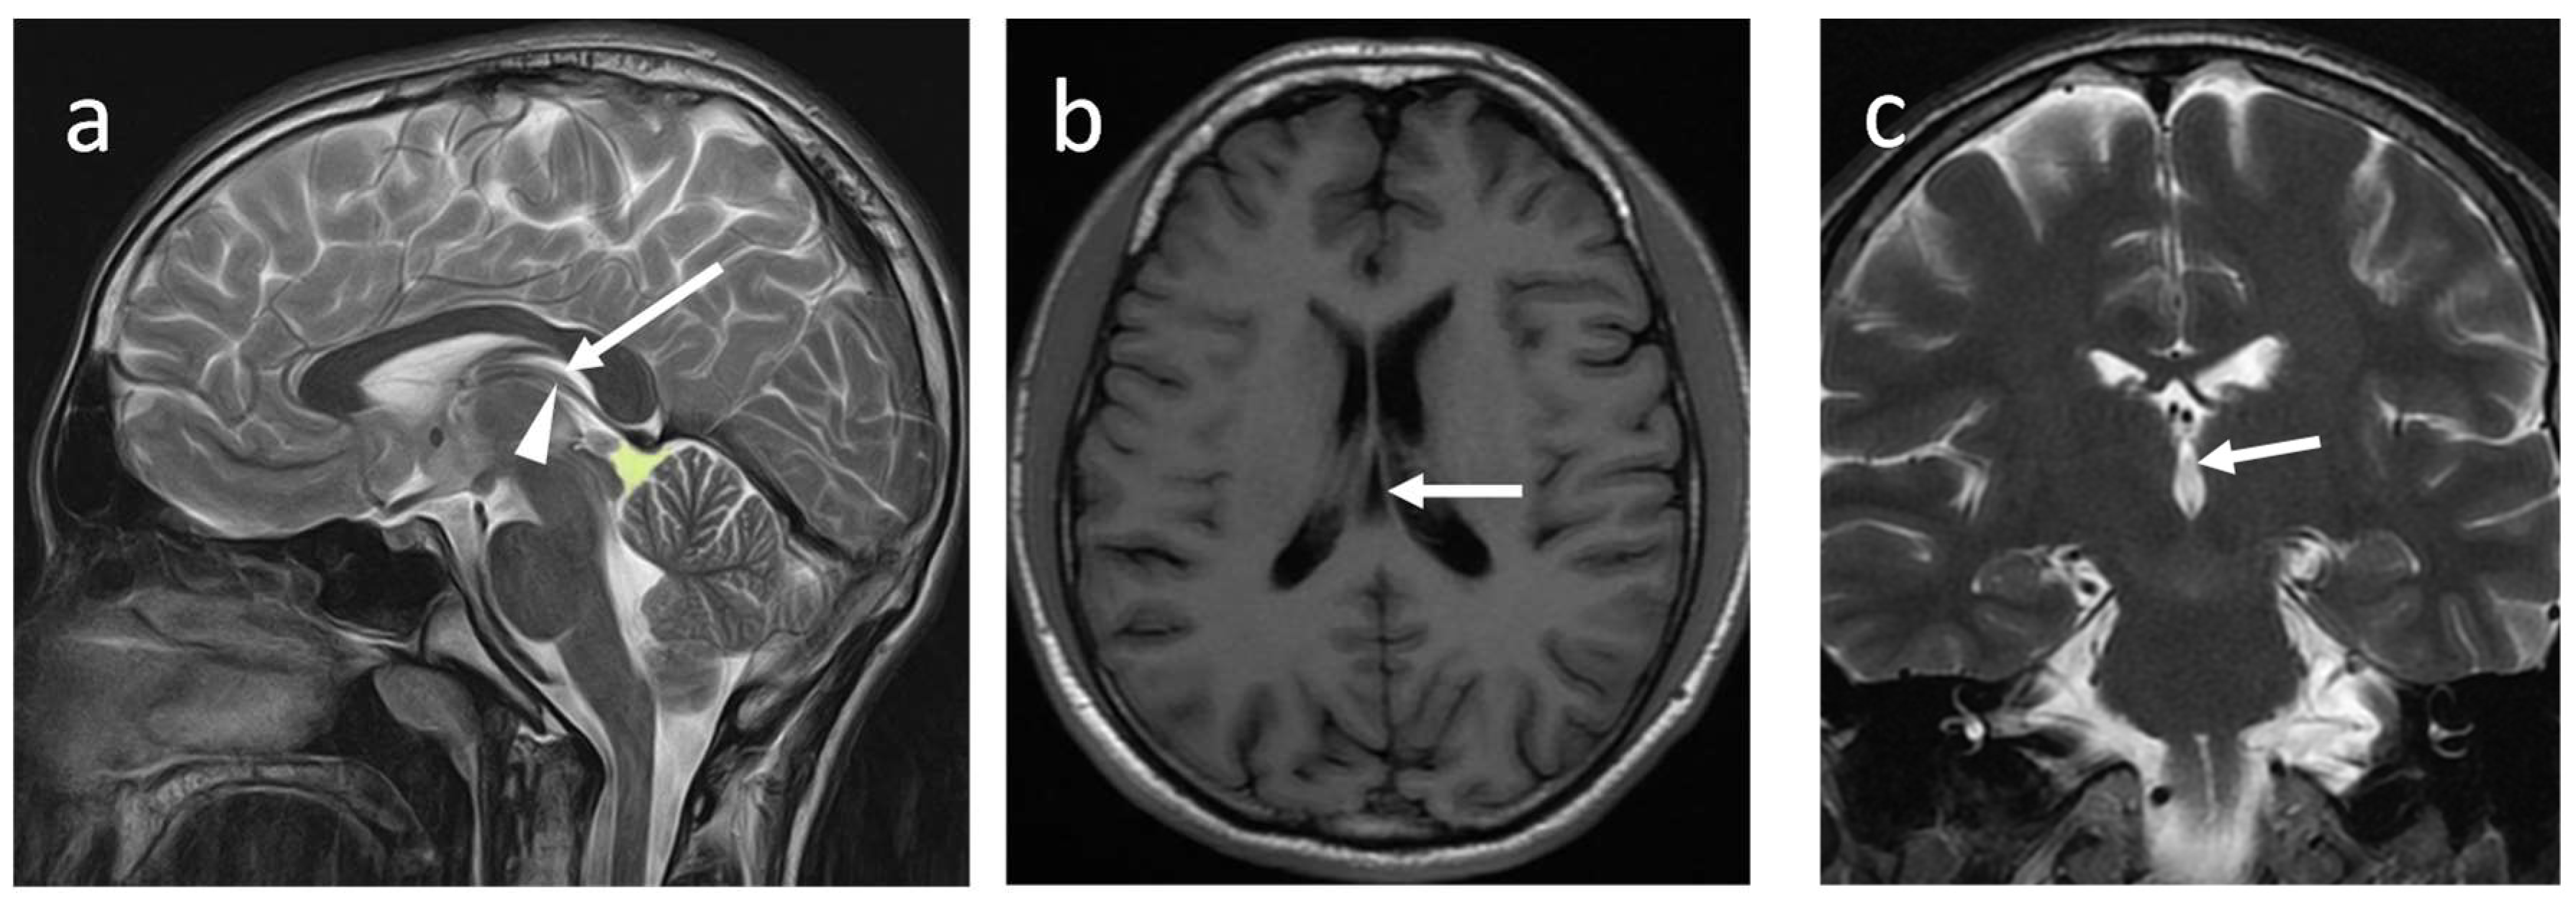

Cavum velum interpositum (CVI)

The velum interpositum space is a triangular shape midline potential space, and when this space is expanded, it is called CVI (Figure 5a-c).

This CSF-filled space is an anterior continuation of the quadrigeminal plate cistern. The CVI is located between two layers of the tela choroidea. The inferior layer of the tela choroidea attaches to the roof of the third ventricle, and the superior layer attaches to the inferior column of the fornix and the hippocampal commissure (psalterium). Anteriorly, tela choroidea fuses at the level of the foramen of Monro and forms the apex of triangular CVI. Its base or posterior end remains open and communicates with the quadrigeminal cistern, superior to the pineal gland (10,11,12). CVI is closely related to the internal cerebral veins and the posterior medial choroidal artery. A layer of ependymal cells does not line this space or contribute to CSF production. Therefore, it is not considered a part of the cerebral ventricular system (10).

The CVI disappears between the last two months of pregnancy and up to the 3rd year of postnatal life. Using ultrasonography, Chen et al. demonstrated a prevalence of CVI of 21 % in preterm infants (12). Another study performed at Yas women's Hospital, Teheran found the prevalence of CVI in the second trimester was 18–23%, and this was nearly similar to its prevalence in infancy (13).It is rarely seen in adults; however, based on MRI brains, Oktem et al. demonstrated a prevalence of 1% among adults aged between 18 and 80 years (3). A CT examination conducted on 442 adults revealed that the occurrence rate of CVI was 7.24% (6).

Figure 5a-c. Non-contrast MRI bran of a 46-year-old male (a) sagittal T2W, (b) axial T1W, and(C) coronal T2W images show CVI (arrow). The arrowhead indicates the internal cerebral vein. Note the posterior location of the quadrigeminal cistern(green).